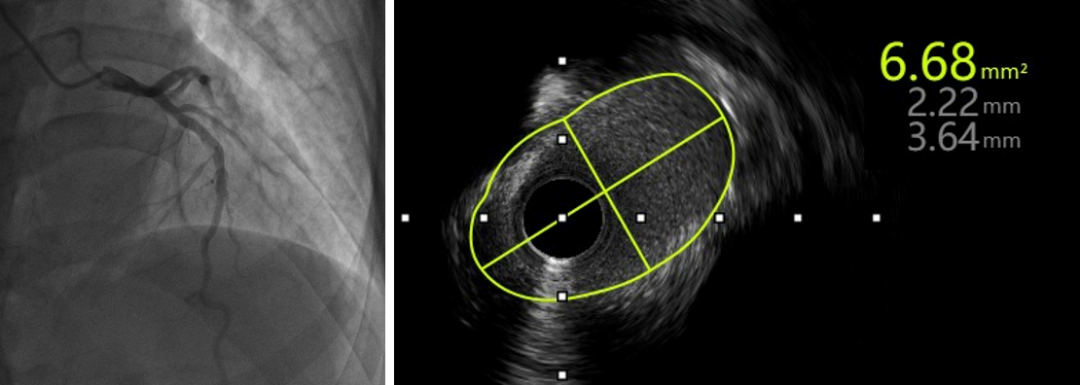

考虑到钙化结节仍较大,钙化环未充分打开,为彻底解决患者的血管病变,崔永亮医师再次穿刺股动脉,经8F指引导管送入2.25mm旋磨头,再次对前降支病变由14万转降速至10万转对病变反复打磨抛光。根据以往经验,透析患者极易反复发生支架内再狭窄的问题,结合IVUS复查结果,崔永亮医师决定采用4.0×30mm药物球囊进一步处理病变,以达到“介入无植入”的效果。术后IVUS显示钙化结节少量残留,管腔面积增大一倍有余上,达6.68mm²,堪称效果完美。

术后造影;术后IVUS管腔面积